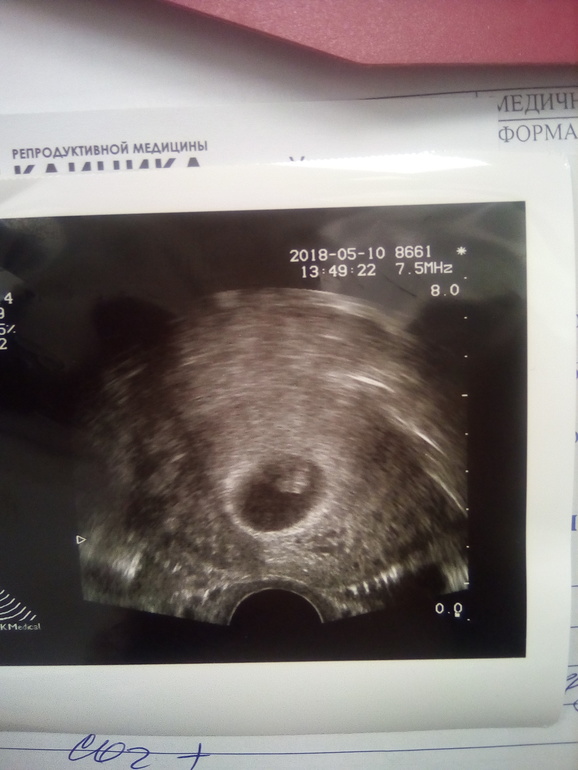

Севодня первое УЗИ. Урааа. 30 дпп.